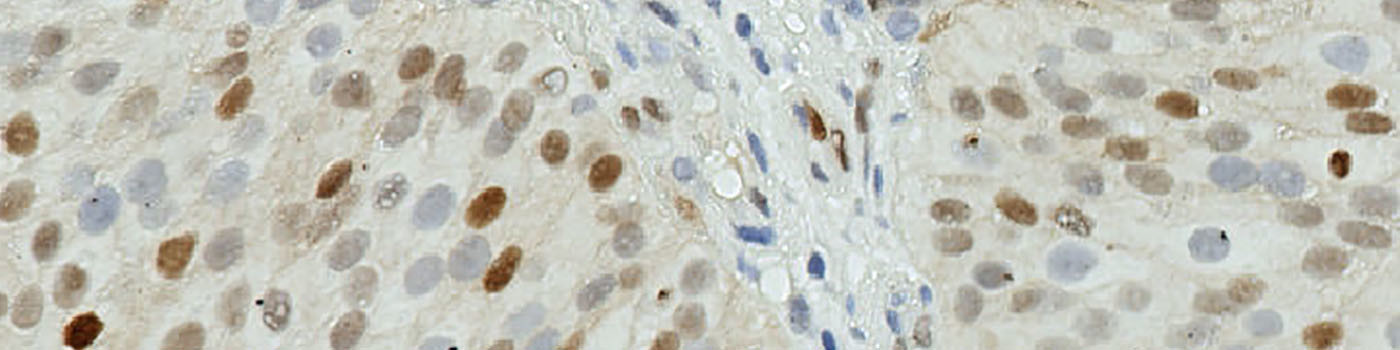

Image of TMA core with bladder tumor tissue after staining by IHC for CyclinD1.

The method used for computing the Cyclin D1 expression is started by detecting nuclei using a novel pattern recognition method adapted from Dahl et al, see [6], which is followed by a step that separates adjacent nuclei, see [7]. The detected nuclei are classified as either positive or negative based on a computation of DAB intensity, obtained using color deconvolution.

This leads to the calculation of the positive area fraction, as the area of positive nuclei divided by the total area of nuclei (within the outlined ROI). This is followed by the measurement of the average DAB intensity across all positive nuclei, which is subtracted from 255, to associate higher values with a high staining intensity, which is more intuitive. The expression is then calculated by multiplying the intensity with the area fraction.

The actual implementation of the pattern recognition allows the user to choose settings for nuclear detection sensitivity and classification into positive and negative, in order to account for differences in local staining protocols.